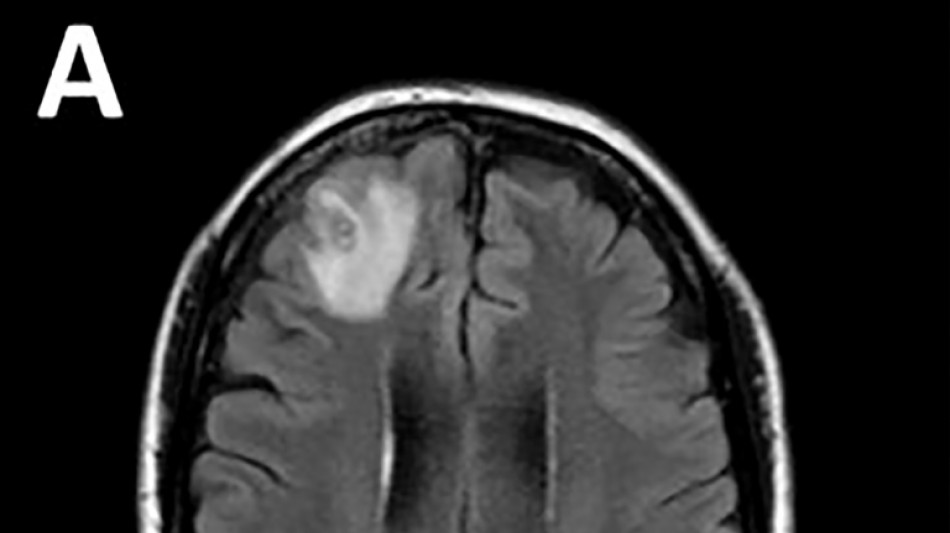

Bombay Durpun - Médicos australianos hallan por primera vez una lombriz parásita en el cerebro de una mujer